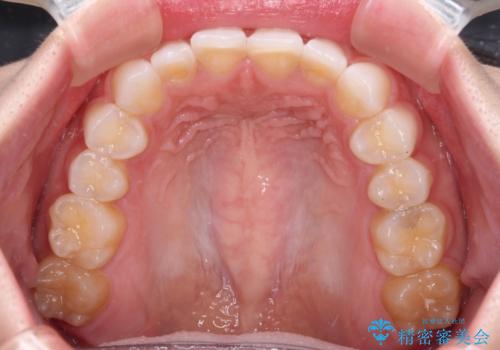

- 矯正治療で歯列を整えた後、前歯の形が気になった患者様です。

矯正前の歯列の影響で、前歯の先端が非対称にすり減ってしまったため、矯正治療後の形が非対称になっていました。

むし歯はなく、矯正治療で咬み合わせが改善していたので、侵襲量の少ないラミネートベニアにて治療することとしました。